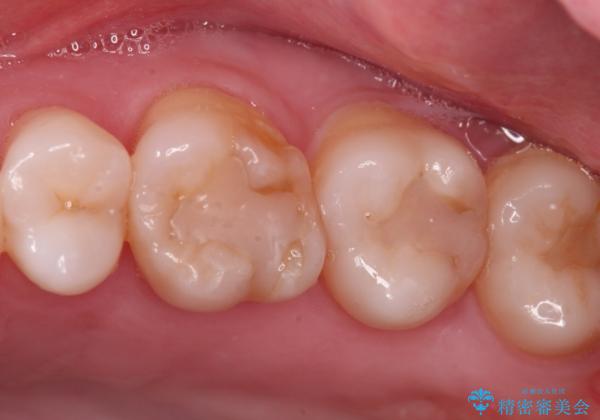

- 昔他院で虫歯治療をしたところが虫歯が再発したとのことで来院。

古い材料(プラスチックの樹脂)をとり、拡大鏡下で虫歯を全て取り除き、

ゴールドインレーにて治療しました。

歯の外側の面が少し欠けていて、そこの部分を覆う(ゴールドの範囲が広くなる)か

そこの欠けてる部分は虫歯ではないので削らないで、最小限にして詰め物を作るか相談したところ

欠けているところは何十年も昔から欠けていて特に何もない。なるべく歯を削りたくないとの事だったので

最小限で詰め物の治療をしました。